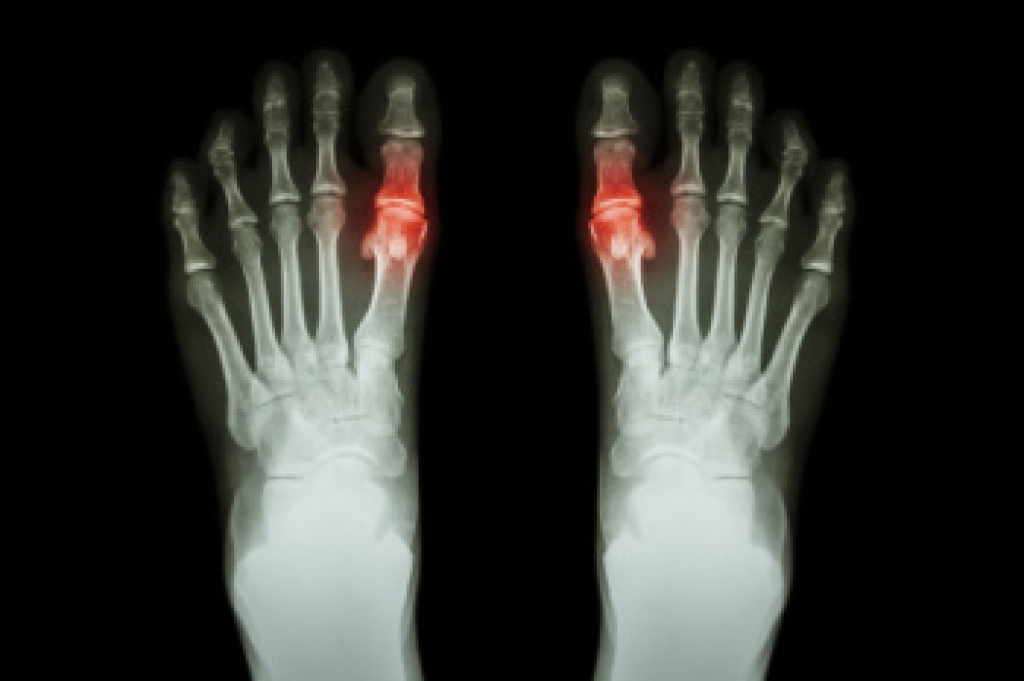

Diabetes affects millions of people every year. The condition can damage blood vessels in many parts of the body, especially the feet. Because of this, taking care of your feet is essential if you have diabetes, and having a podiatrist help monitor your foot health is highly recommended.

Patients with diabetes should have their doctor monitor their blood levels, as blood sugar levels play such a huge role in diabetic care. Monitoring these levels on a regular basis is highly advised.